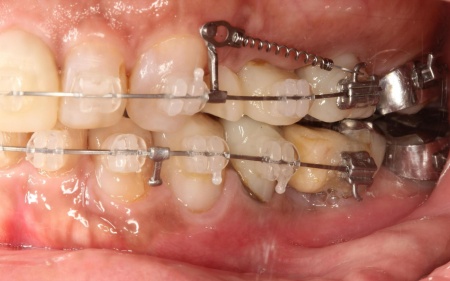

その後、ワイヤー矯正とクローズドコイル(バネの装置)を使ったスピード矯正を行い、前歯を後方に移動させます。

下顎は残根も利用しながら、矯正用の小さなネジ「テンポラリーインプラント(インプラントアンカー)」を顎の骨に埋め込んで固定源とする方法も併用し、歯を移動させました。

矯正期間中は定期的に装置の調整を行い、歯の動きや噛み合わせの変化を確認しながら治療を進めています。